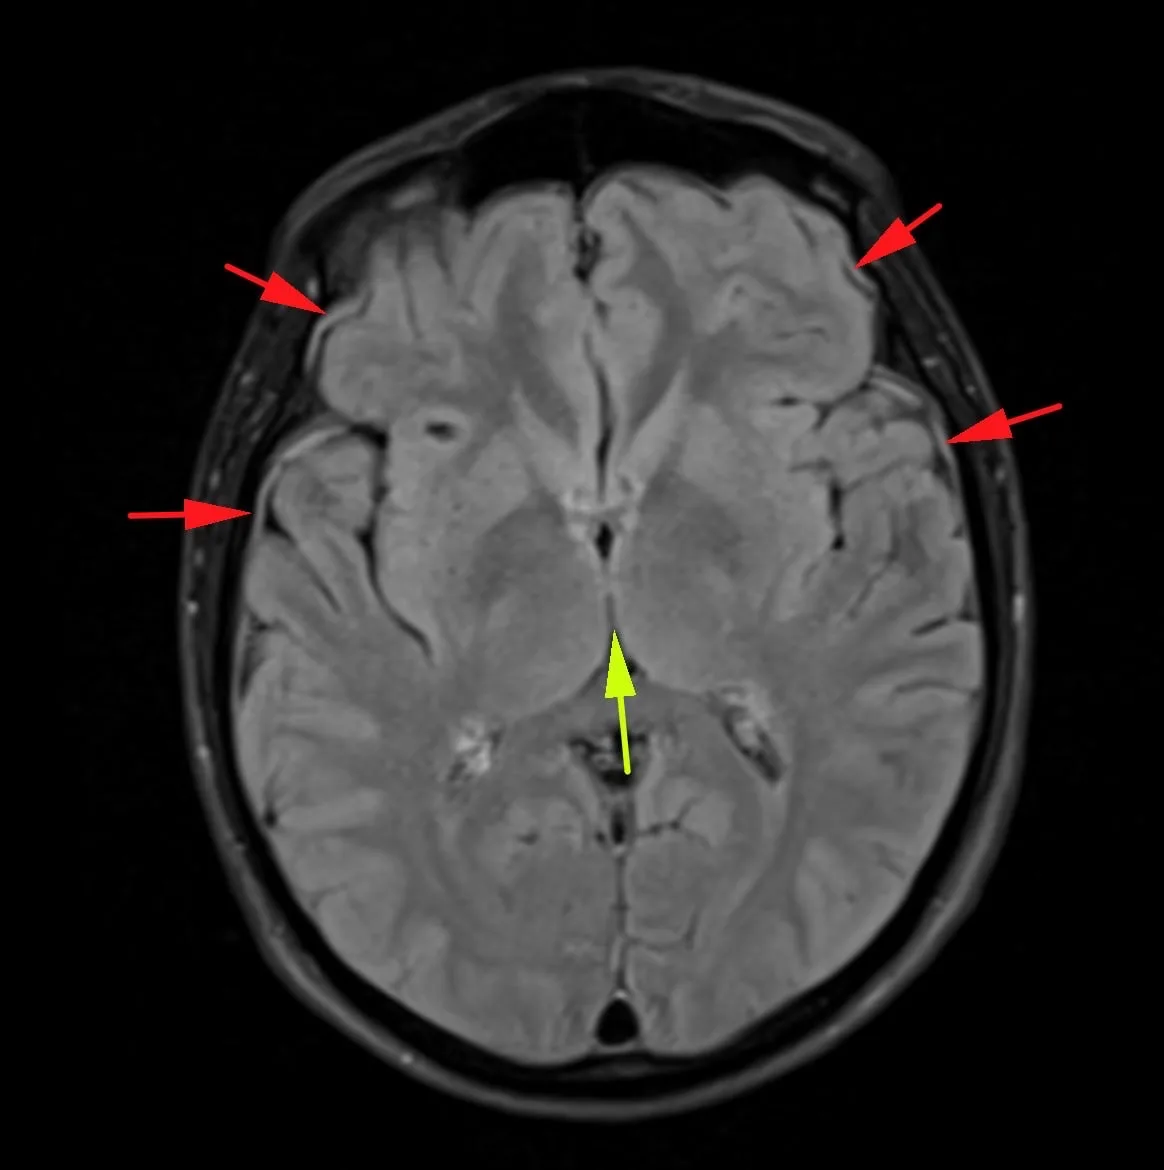

Женщина 32 года. Больной считает себя с 2024 г, когда стала отмечать онемение угла рта. Со слов пациентки ей был предварительно выставлен диагноз - РС, но дополнительных методов обследования и специфического лечения не проводилось. В настоящее время жалоб нет. В исследовании от октября 2024 отмечался очаг в левой затылочной доле с выраженным контрастированием, в настоящее время этот же очаг отмечается с сохраняющимся контрастированием. Формально - есть выполнение критериев диссеминации и в пространстве (юкстакортикальный и перивентрикулярный очаги есть), и во времени (есть усиливающиеся и неусиливающиеся очаги), клиника тоже вполне укладывается. Но! Найти в литературе подобных случаев мне не удалось, видел сам и максимум, что находил в литературе - полгода контрастирования. Получается, мы имеем дело с крайне атипичным рассеянным склерозом, или это не рассеянный склероз. А тогда что? Сосудистая мальформация не вариант - на SWI не видать. Какая-то ганглиоглиома? А другие очаги тогда что? Есть соображения? Кстати, диффузия стойко повышенная, и на б1000 почти не видно (изо). На Т2 не меняется